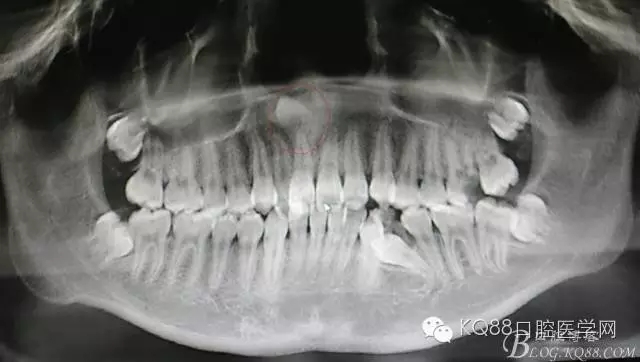

圖1.CBCT全景片重建檢查:11根尖區(qū)上方有一倒置多生牙

圖2.CBCT矢狀面影像檢查:多生牙牙冠上方與鼻底僅有黏膜相隔

圖3.CBCT三個(gè)方向剖面圖影像:多生牙牙根阻擋11內(nèi)收、牙冠接近鼻底

患者、女、13歲,主訴:上前牙擁擠,要求矯正。??茩z查:21腭側(cè)錯(cuò)位萌出,CBCT檢查:11根尖區(qū)有一倒置多生牙,多生牙會(huì)影響正畸治療,建議外科手術(shù)拔除多生牙?;颊咄庵委煼桨浮⒑炛橥鈺?shū)。